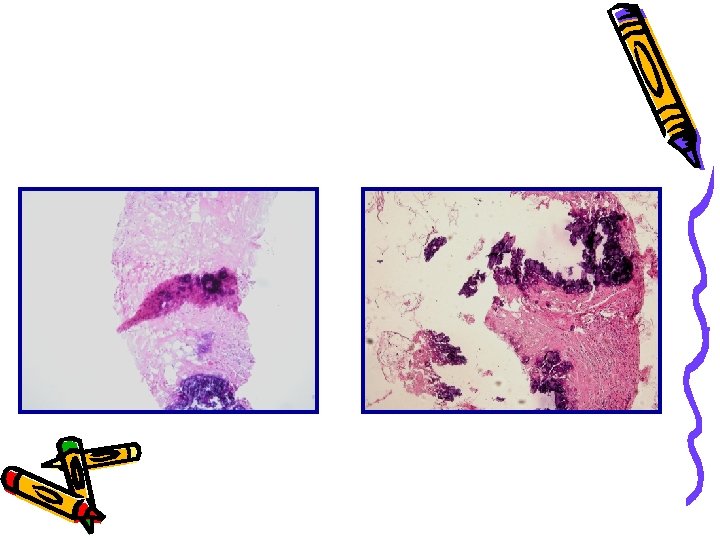

Striscio cervico-vaginale Citoincluso lav. bronchiale. Pos

Citol. per apposizione linfonodale. Melanoma Citol. urinaria. Pos. Versamento pleurico